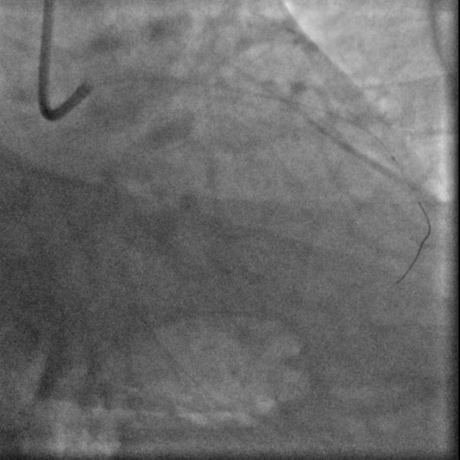

G3前进

Pilot扭身进入lad

Pilot200进入真腔

经右股动脉(8F),送EBU 3. 5指引导管指引导管至左冠开口。Sionblue导丝至LCX保护,Finecross 130到达LCX远端待命。Sionblue引导Corsair 135cm微导管进入LAD。近段纤维帽坚硬(伴钙化随后IVUS证实)尝试使用Gaia1st进入前次假腔,导丝升级Gaia 3rd谨慎前进入间隔支S1,推送corsair进入S1交换KDLC,Pilot 200导丝平行进入LAD真腔。Corsair交换Sionblue到LAD远端。IVUS证实全程真腔,闭塞段以纤维为主。植入支架完成血运重建。